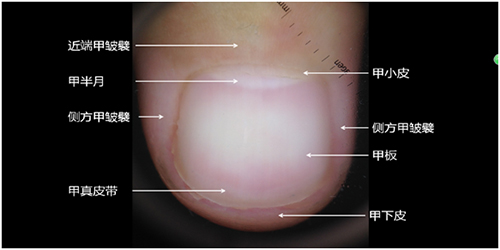

答:上图是组成甲单元的结构名称,其中最重要的部分就是甲半月。甲半月的大小因人而异,和健康无关。甲半月的本质是透过甲板显现出来的远端约1/3至1/2的甲母质。甲母质由具有分化能力的甲母质上皮组成,其可分化形成甲板。宝爸宝妈们可以理解为甲母质是甲板的“妈妈”,甲母质出现了问题,甲板也会出现问题。正常甲母质中是含有黑素细胞的,只不过平时这些黑素细胞处于静止状态,如黑素细胞活性增强或增殖则导致产生黑色素增加,色素颗粒被运输至甲板和甲床,最终甲板上就出现了纵行色带,称为“纵行黑甲”。